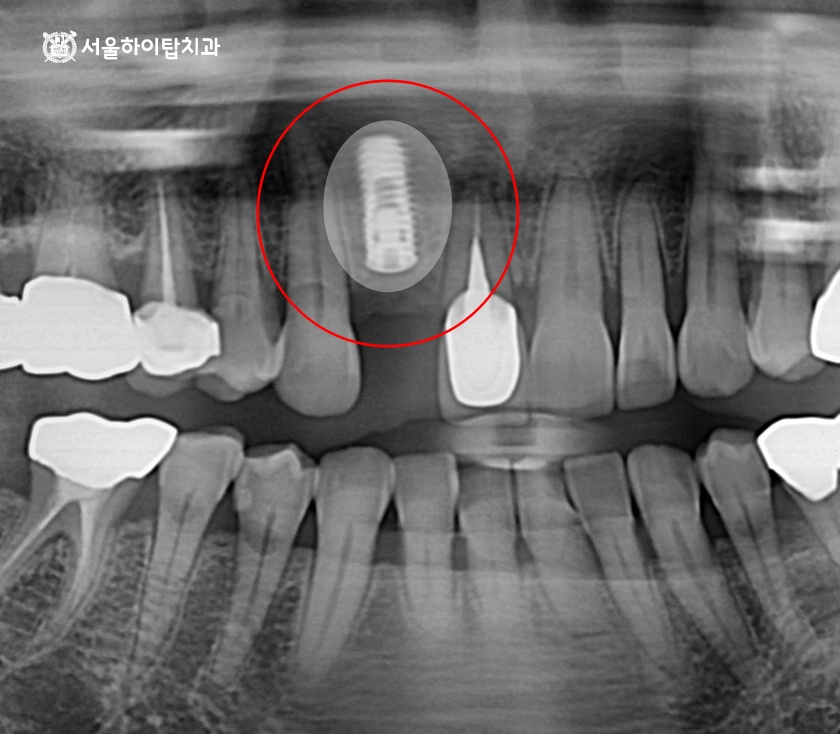

수술 완료

CT를 통해 계획된 위치에 치조골 이식을 동반하여 안전하게 심겨진 모습입니다.

새로운 뼈가 이식된 만큼, 임플란트와 뼈가 단단히 융합되는

골 유착 기간을 충분히 확보하는 것이 중요합니다.

보통 이 과정에는 약 3~4개월 정도의 시간이 소요되며,

이 기간 동안 심겨진 고정체가 움직이지 않는지 꾸준한 경과 관찰 또한 중요합니다.